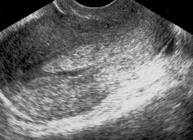

- Transvaginal ecography which is sometimes followed by aninjection of a saline solution into the uterus in order to obtain a clearer image of the contents of the uterine cavity (hysterosonografy).